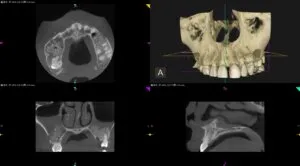

まさに成長因子という「アプリケーション」を用いると最大限の効果が発揮できる打って付けの題材です。それは、上顎洞内という密室の洞窟には多数の骨を作る細胞が存在し、その組織も成長因子と相性が抜群だからです。手術の内容も、時間も正確に執り行うことができ、安堵しています。

患者様は、先天的部分無歯症で歯列、噛み合わせ、咀嚼障害を訴えています。このようなライブOPをさせて頂き、心より感謝申し上げます。これから治療計画通りに遂行し、苦痛を解決するために最大限の努力をするつもりです。この場を提供させて頂きましたBTI Japanのスタッフと受講生の先生方、当医院のスタッフにも感謝申し上げます。